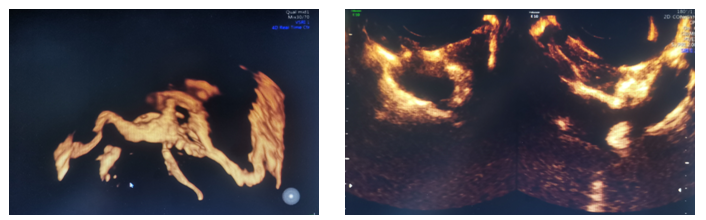

患者为31岁不孕症女性,在西咸院区产科就诊后,临床医生接诊后认为需要超声检查以评估宫腔情况及双侧输卵管通畅性。超声诊断中心任媛主治医生全程配合,为患者行四维超声宫腔成像及输卵管超声造影检查,整个过程顺利,耗时短,患者无不适,该项检查为临床及患者提供了客观影像学信息。

输卵管超声造影检查是通过向宫腔内注射超声造影剂,使宫腔及输卵管显影,可清楚观察到宫腔、宫角、双侧输卵管的形态及与卵巢的位置关系,欧美视频